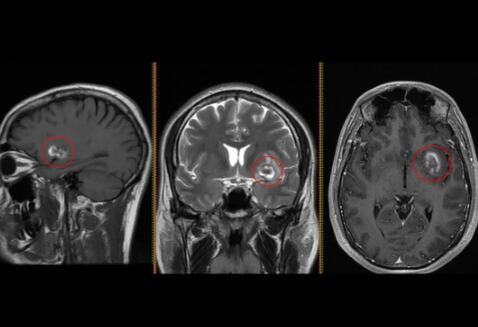

En julio de este año Ale contó, a través de Instagram, que recibió una de las noticias más duras pues los doctores le descubrieron un tumor en el cerebro.

“Me descubrieron un tumor con sangrado en el cerebro que me afecta mi vida de varias maneras, incluyendo mi memoria a corto plazo, que me estaba fallando desde hace varios meses. En dos meses me operan y la recuperación tardará varios meses más. La otra semana viajo a Estados Unidos para unos chequeos y posteriormente la operación.